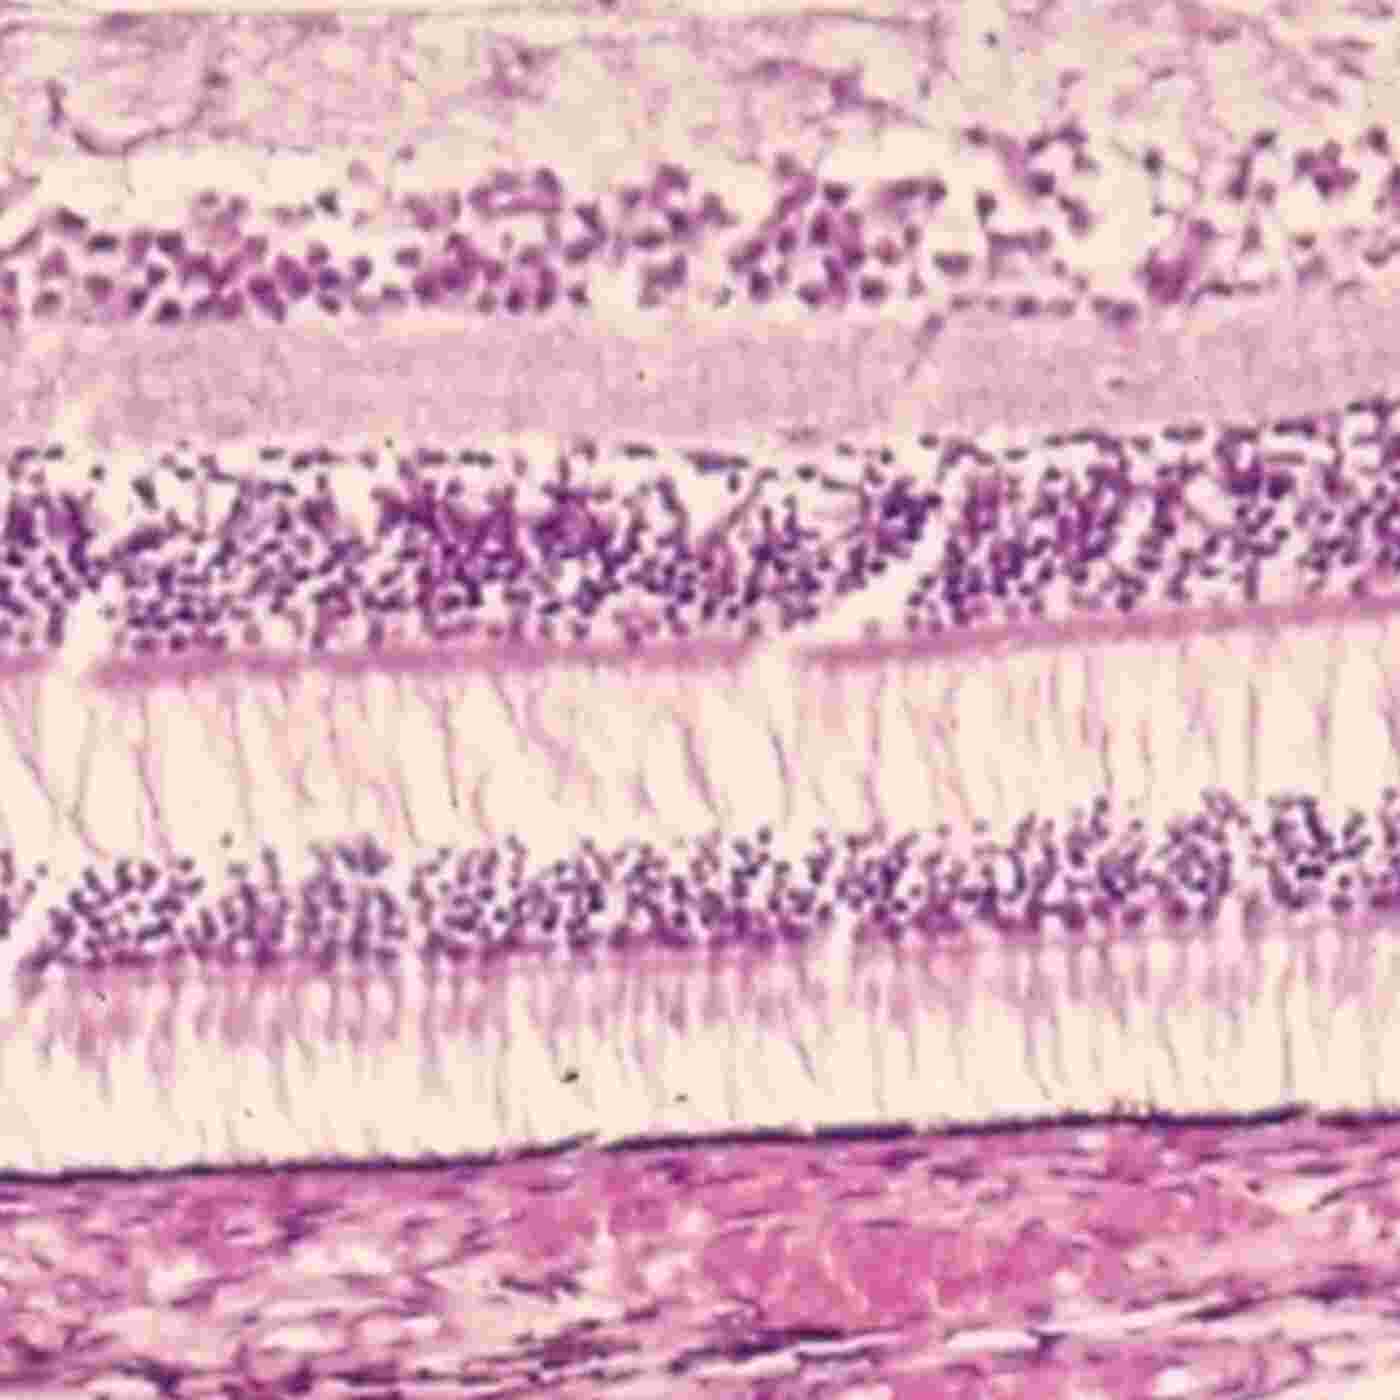

HistolCast 27. Retina